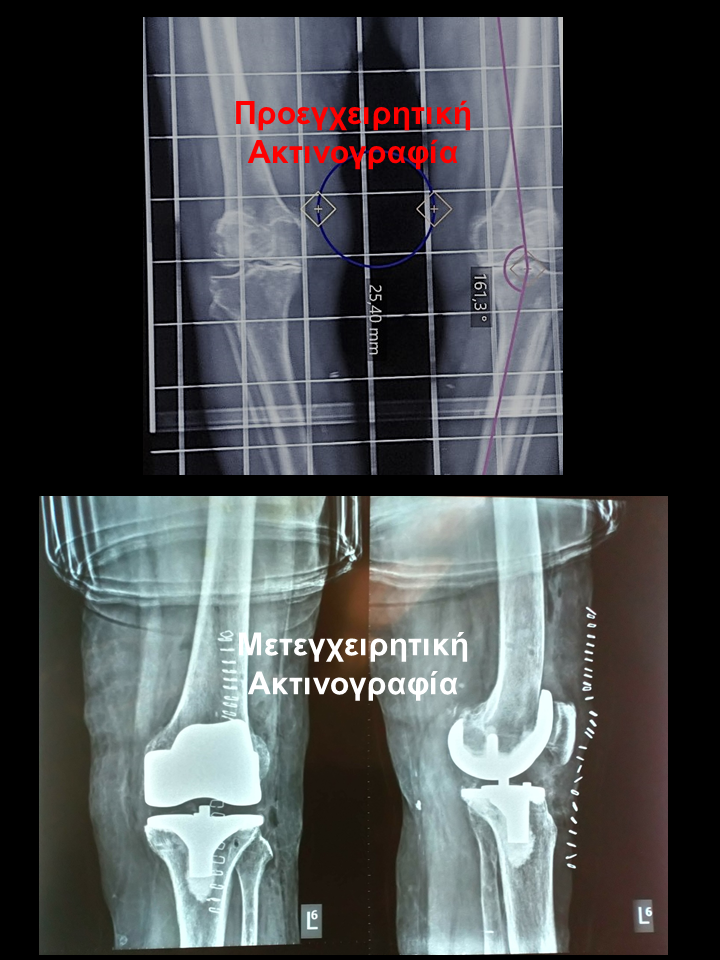

Ασθενής με οστεοαρθρίτιδα δεξιού γόνατος και μεγάλη παραμόρφωση

Ασθενής 74 χρονών με μετατραυματική οστεοαρθρίτιδα και μεγάλη παραμόρφωση. Είχε επιδεινούμενο άλγος δεξιού  γόνατος που την δυσκόλευε στη βάδιση, στο κάθισμα και την αφυπνούσε το βράδυ. Υπεβλήθη σε ρομποτική αρθροπλαστική γόνατος. Χρησιμοποιήθηκε η τεχνική διατήρησης οστού όπου αφαιρέθηκαν λιγότερα χιλιοστά οστού. Ο άξονας από 9.50 αποκαταστάθηκε στις 20 , το έλλειμα έκτασης από 9.50 σε 1.50  και η κάμψη στις 1170. Η ασθενής έλαβε εξιτήριο τη δεύτερη ημέρα και βαδίζει πλέον χωρίς καμία ενόχληση.